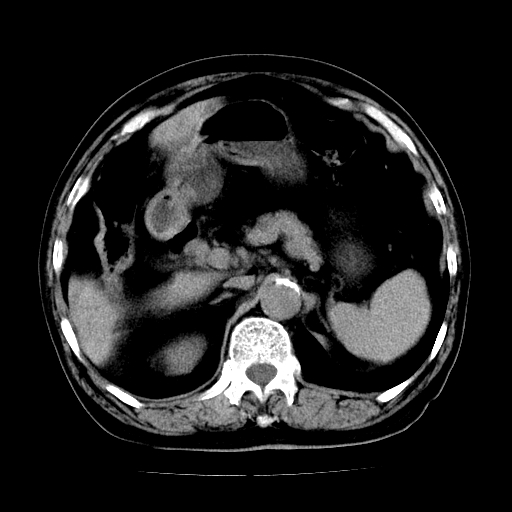

男,71岁,皮肤黄染四天。

肝内外胆管及胆总管上段扩张,考虑为梗阻所致,建议mrcp检查。

考虑胆总管癌并肝内外胆管扩张。

胆管癌并肝内外胆管扩张。

支持考虑胆总管癌并肝内外胆管扩张。 局部应薄扫。心包钙化。

胰腺上端胆总管内见软组织影,强化不明显,结合临床,还是考虑低位梗阻性黄疸,胆总管癌可能性大